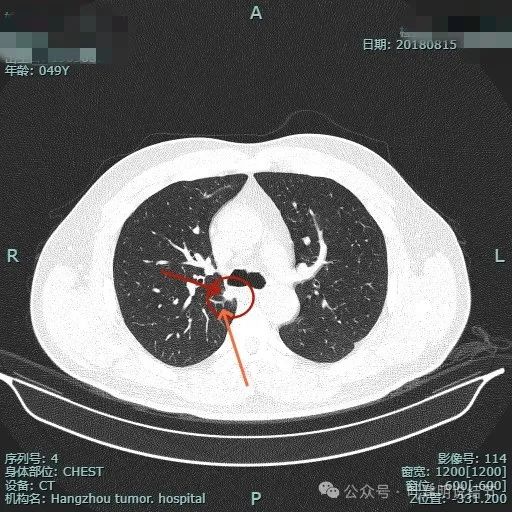

再看2018年时连续层面的:

病灶出现。

实性密度,边缘略糊。

表面毛刺。

紧贴胸膜。

血管进入。

整体轮廓较清。

细毛刺明显。

缺乏膨胀性。

边缘区密度较淡。